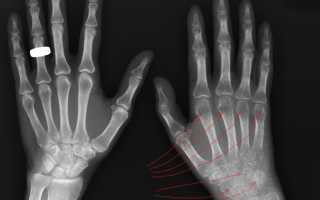

Синдром зудека после перелома лучевой кости руки